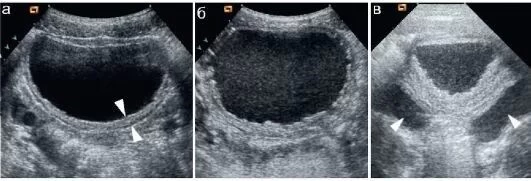

Ультразвуковое обследование мочевого пузыря дает возможность врачу визуализировать структуры выводящей системы неинвазивным способом. Работа УЗИ основана на различном отражении невидимой звуковой волны от тканей и образований различной плотности, что показывает строение данного органа с наличием:

- изменений в толщине стенки;

- нарушений контура, отечности, слоистости стенки;

- наличия пристеночных объемных образований, взвеси в моче;

Ультразвук обеспечивает четкое изображение стенок органа, формы, размера и наличия каких-либо отклонений. Его можно выполнить двумя основными вариантами: трансабдоминально (через низ живота) и внутренним доступом (через влагалище у женщин). Трансабдоминальный подход используется чаще и особенно полезен для оценки объема остаточной мочи и наполненного пузыря.